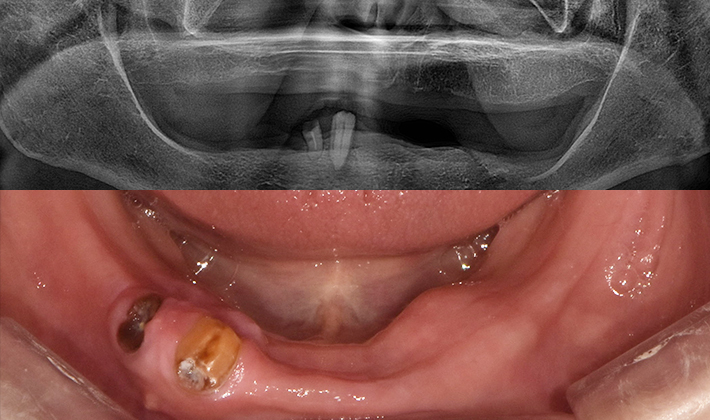

치과가 무서워 10년 동안 미뤄온 임플란트 수술 그 결과는?